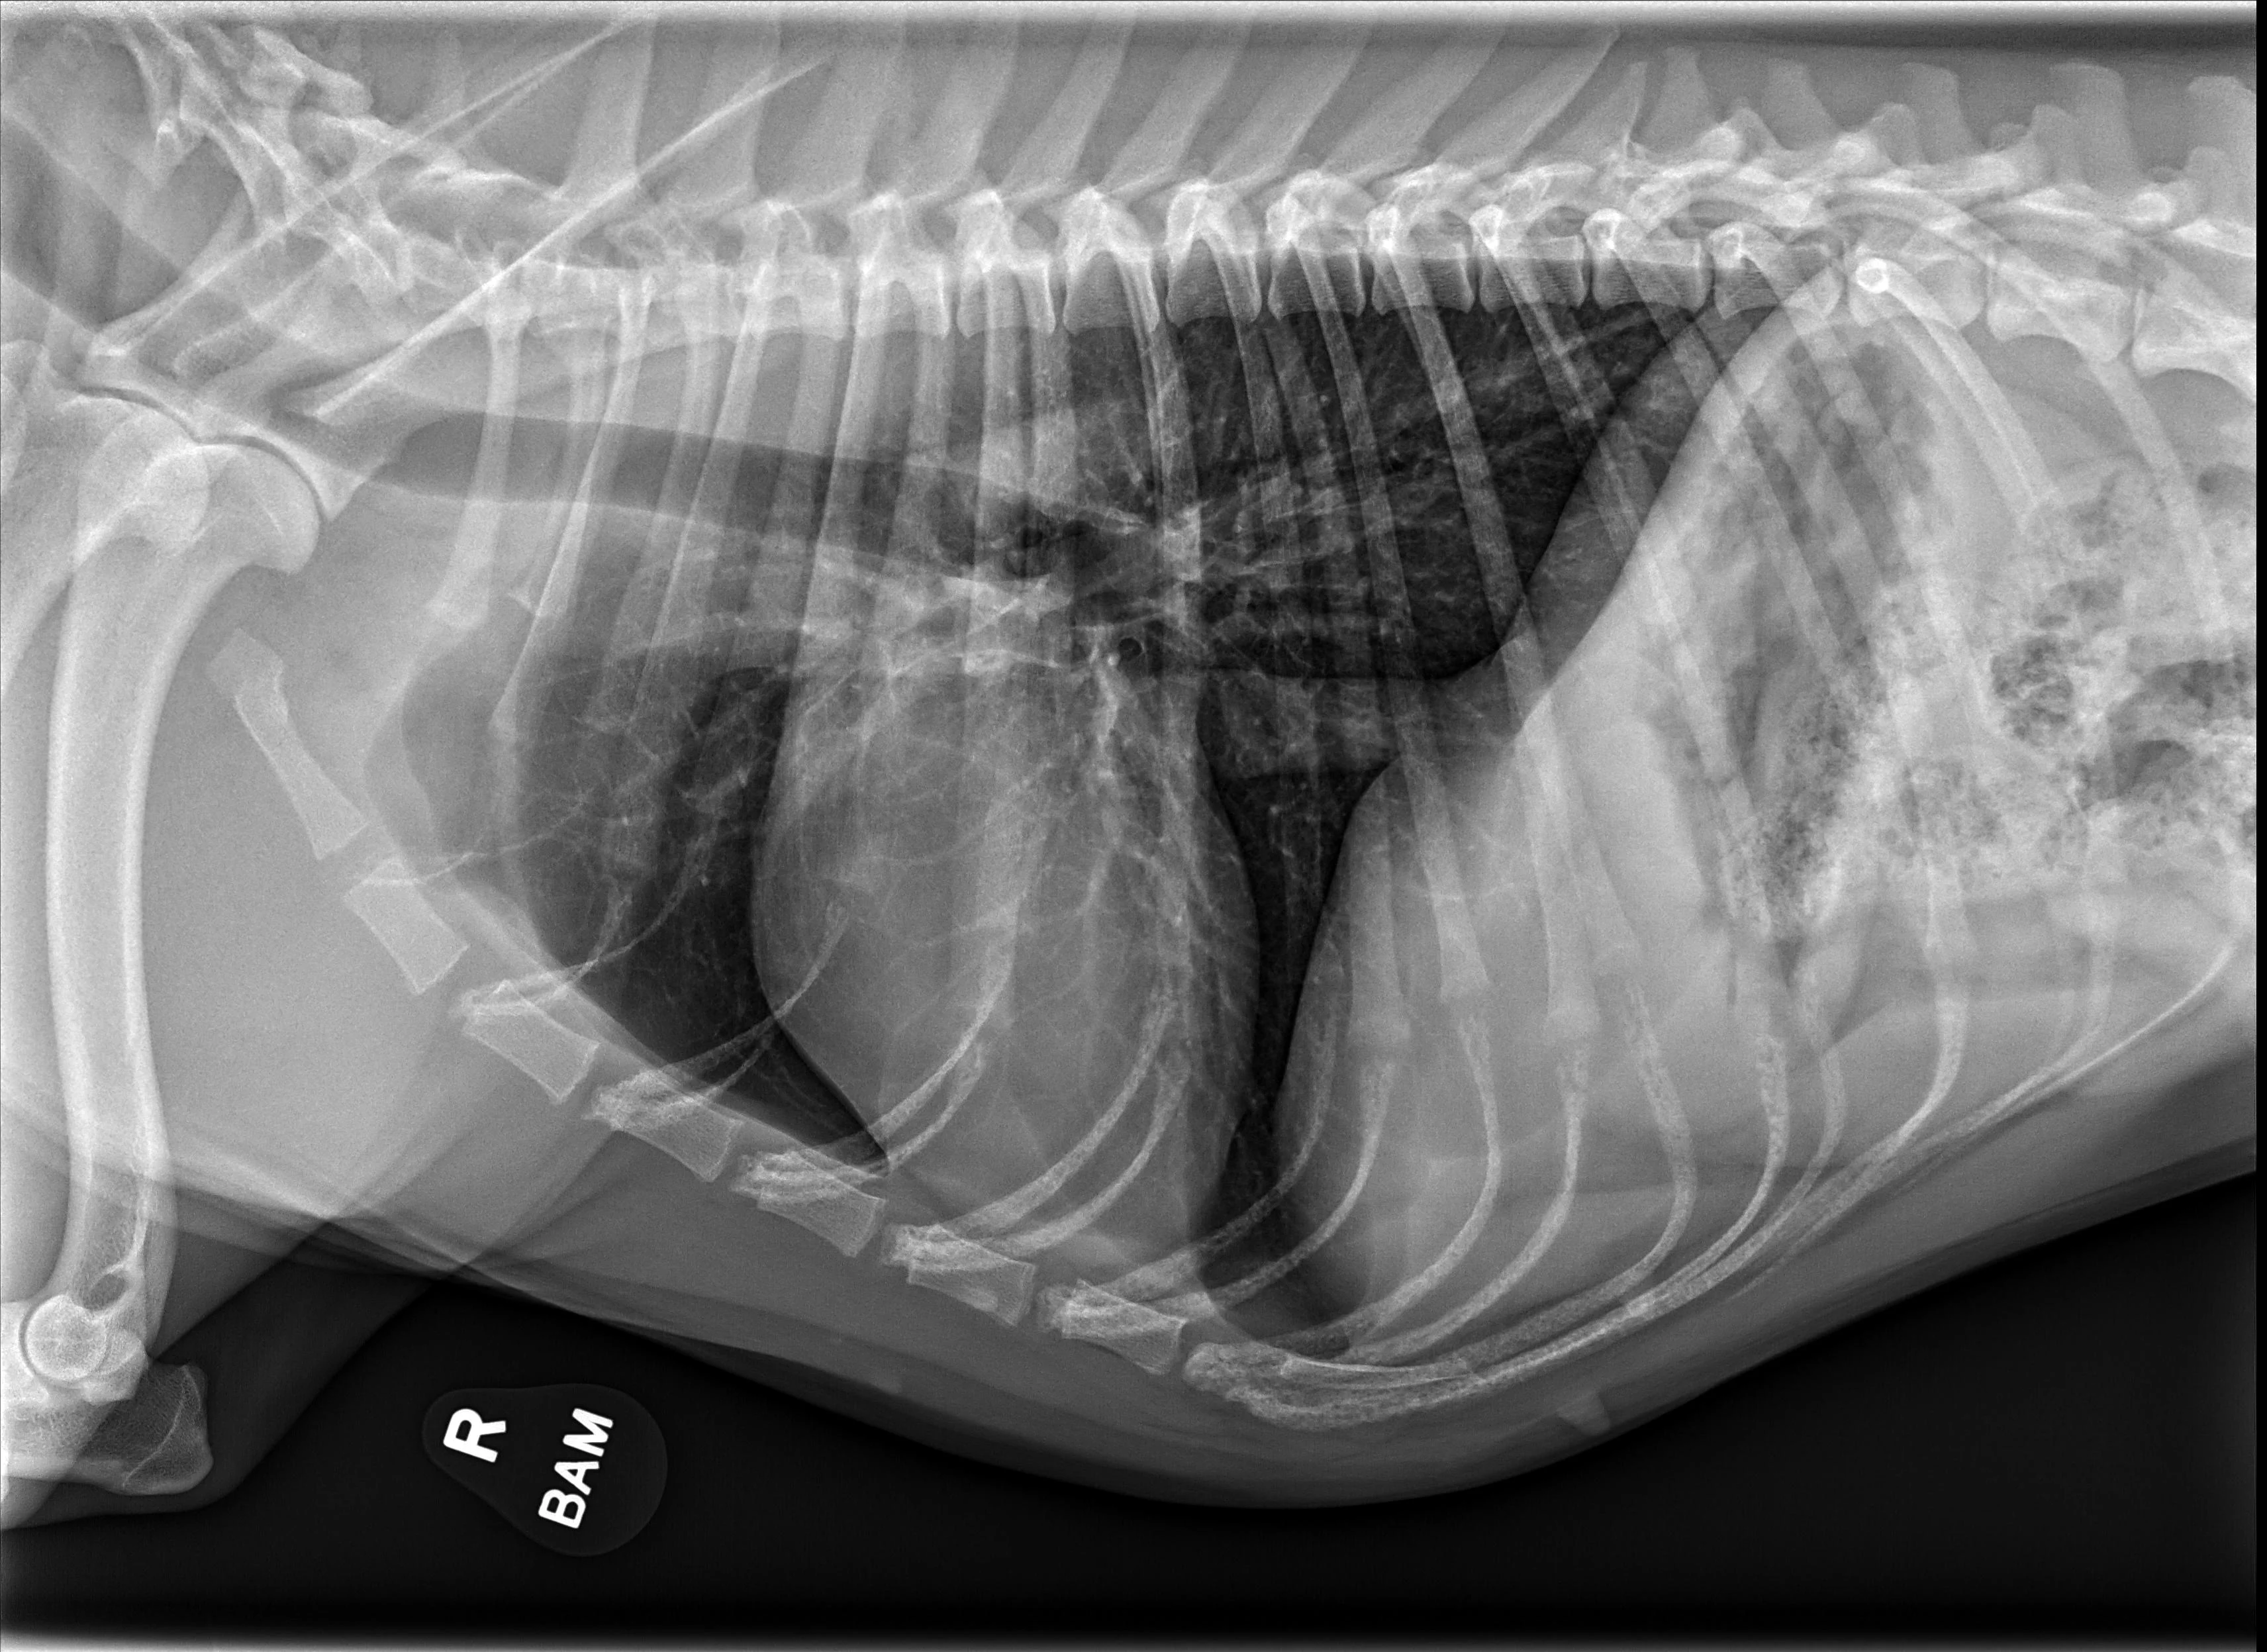

Not all cardiac changes are easy to spot on radiographs. This practical guide highlights key signs, explains limitations, and illustrates real-world cases of MMVD, DCM, PDA and more.